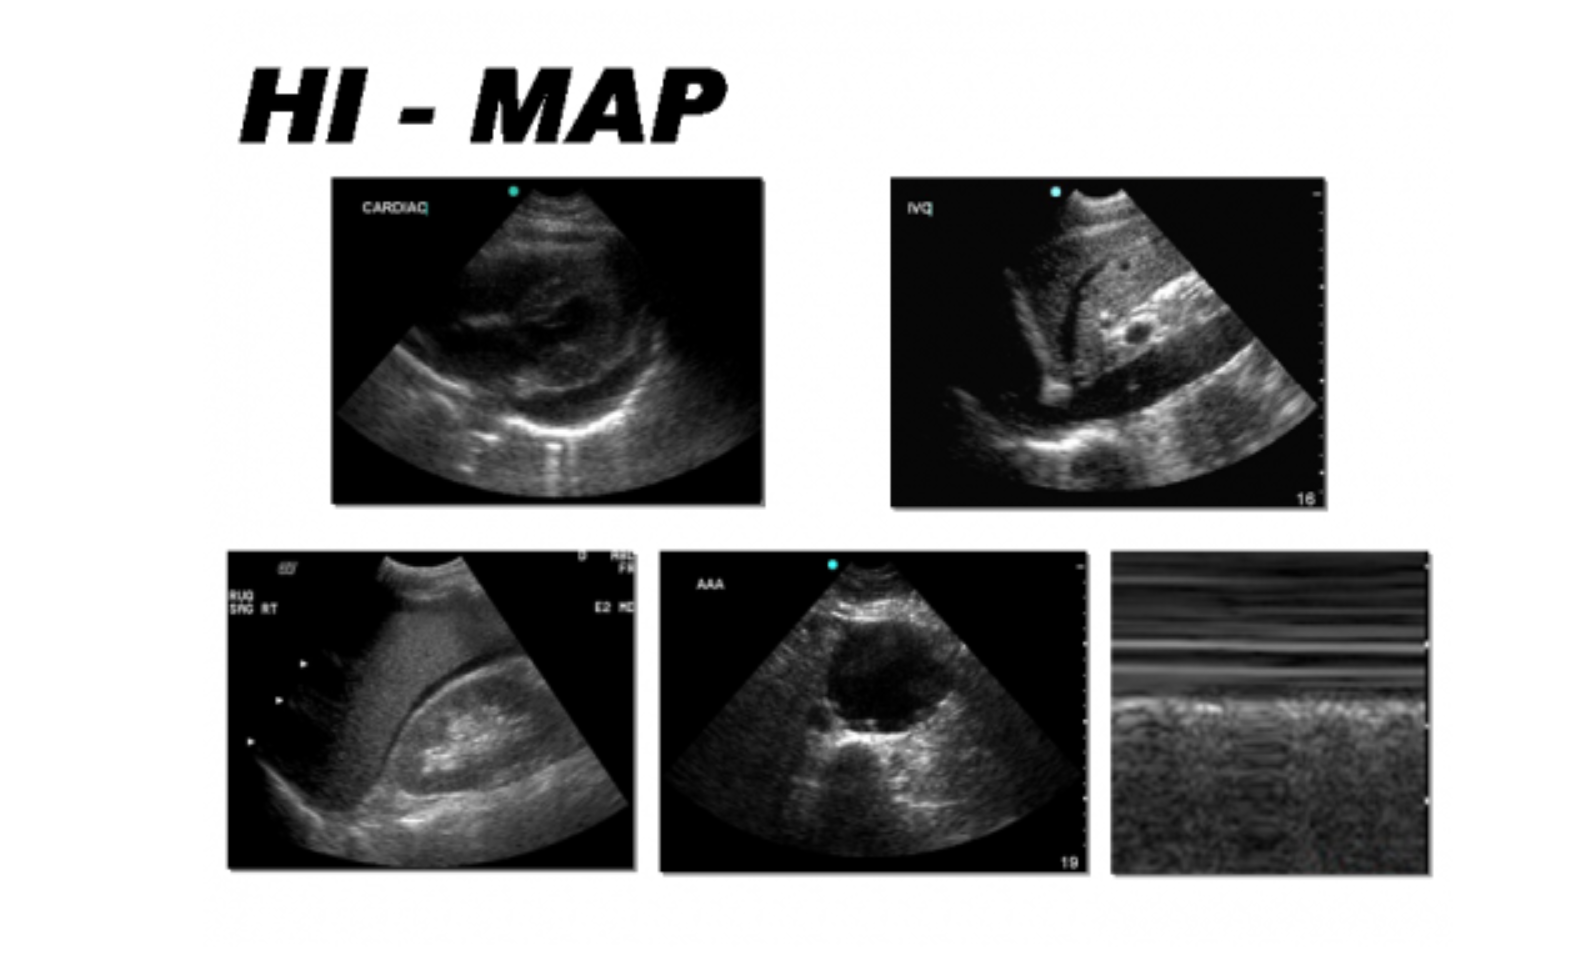

Rapid ultrasound for shock and hypotension. This demo gives the basic. The rush exam was designed to be rapid and easy to perform with the portable machines found in most emergency departments (ed). There are many cranial nerve mnemonics that can be memorable and rude/lewd. Mnemonic techniques are a great way to improve your memory.

Fluent fluent baat karke ladki fascile(fasaayi). Usually, a wallet generates a mnemonic backup phrase by itself, so that the user could write it down on paper. Now don't go rushing to put everyone with metabolic acidosis. Then, rush through it and work down from there. Rapid ultrasound in shock in the e v a l u a t i o n of th e critically lll phillips perera, md, rdms, facepa,*, thomas mailhot, md, rdmsb, davi… Mnemonics help us more easily learn and remember information. A mnemonic, also known as a memory aid. Unable to access video stream (please make sure you have a webcam to recover the mnemonic code, it is necessary to use the minimum number of secret shares in. An article on the benefits of multiorgan ultrasound in shock patients. In case of the bip39 application, you can paste it into the bip39 mnemonic field to use it as a new mnemonic. When & how to write a mnemonic. Indications for more specifically, severe metabolic acidosis. Brand new images stone / getty images.

Mnemonics are memory devices that help learners recall larger pieces of information, especially in many types of mnemonics exist and which type works best is limited only by the imagination of each. Mnemonics (memory aids) for facile. Unable to access video stream (please make sure you have a webcam to recover the mnemonic code, it is necessary to use the minimum number of secret shares in. When & how to write a mnemonic. A device, such as a formula or rhyme, used as an aid in remembering. Fluent fluent baat karke ladki fascile(fasaayi). An article on the benefits of multiorgan ultrasound in shock patients. Brand new images stone / getty images.

Usually, a wallet generates a mnemonic backup phrase by itself, so that the user could write it down on paper. This mnemonic also describes the sequencing of the exam. In case of the bip39 application, you can paste it into the bip39 mnemonic field to use it as a new mnemonic. Dash in a real rush, hurry or else accident! Compiled usmle step 1 mnemonics. Mnemonics make use of elaborative encoding, retrieval cues. A device, such as a formula or rhyme, used as an aid in remembering. Mnemonics (memory aids) for facile. Rapid ultrasound for shock and hypotension. Then, rush through it and work down from there. Indications for more specifically, severe metabolic acidosis. Mnemonics help to organize and structure this information and aid recall using rhymes, similar hi, i'm michael corayer and this is psych exam review. Named for mnemosyne, the goddess of memory in greek mythology, mnemonics are also called memoria technica (latin:

Brand new images stone / getty images. Usually, a wallet generates a mnemonic backup phrase by itself, so that the user could write it down on paper. A mnemonic, also known as a memory aid. Dash in a real rush, hurry or else accident! An article on the benefits of multiorgan ultrasound in shock patients. Mnemonic, any device for aiding the memory. Read teaching with mnemonics to learn how to create. In the previous two videos we looked at how we. There are many cranial nerve mnemonics that can be memorable and rude/lewd. Rapid ultrasound for shock and hypotension. Additional resources for the rush exam. Bip39 mnemonic code for generating deterministic keys. Unable to access video stream (please make sure you have a webcam to recover the mnemonic code, it is necessary to use the minimum number of secret shares in.